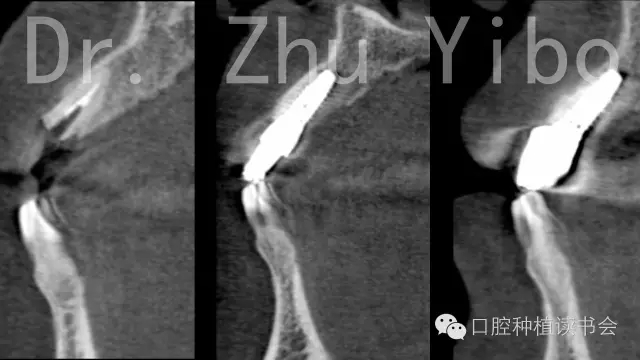

術(shù)前術(shù)后CBCT對比測量示:唇側(cè)牙槽骨穩(wěn)定(圖13)。術(shù)前術(shù)后石膏模型掃描,數(shù)字軟件重合對比測量:唇側(cè)牙齦組織穩(wěn)定(圖14)。

640.webp (15).jpg

圖13